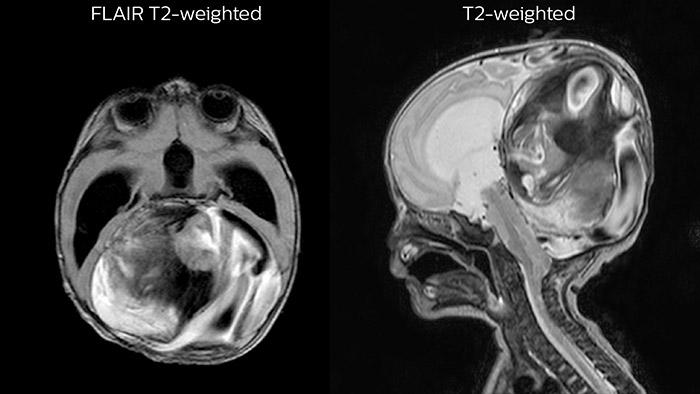

Dural sinus malformation (DSM)

Initial examination

Dural sinus malformation

After three times of coiling and acryl based embolization

After three times of coiling